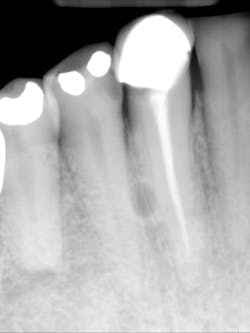

A complete mouth series was made with an incidental, well-defined, circular, radiolucent area noted between the roots of the mandibular right canine and first premolar.

For lateral periodontal cysts, there is a male predilection with a mean age of 50 years. They are typically asymptomatic and incidental findings. They are most commonly found between the lateral incisor and second premolar (mandible) and lateral incisor region (maxilla). The cyst appears as a well-defined, round/ovoid radiolucent entity. It may obliterate the lamina dura of adjacent teeth. As it enlarges, it may cause displacement and/or resorption of adjacent teeth. It is frequently single, but may be multiple. The size is typically less than 1 cm in diameter.